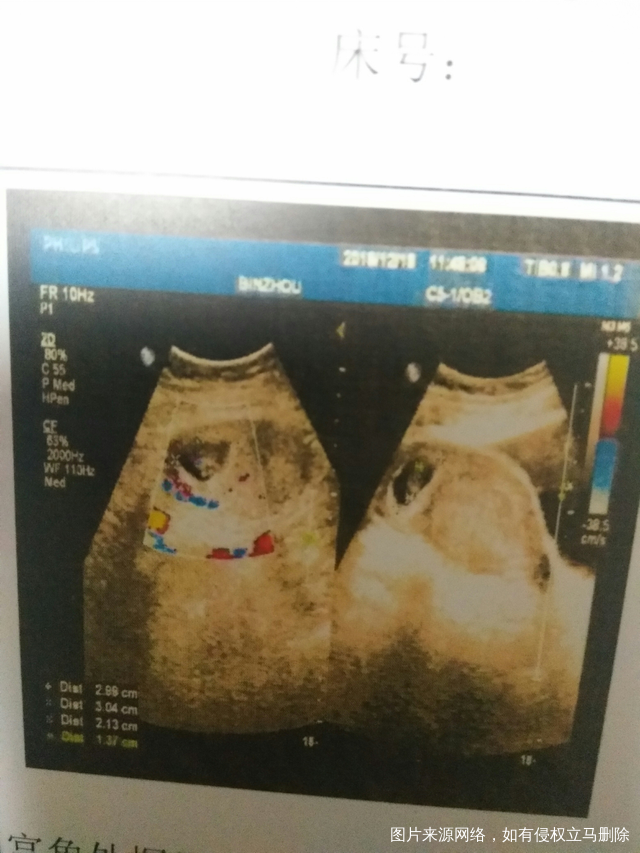

右侧宫角妊娠,想保住孩子,希望大吗?